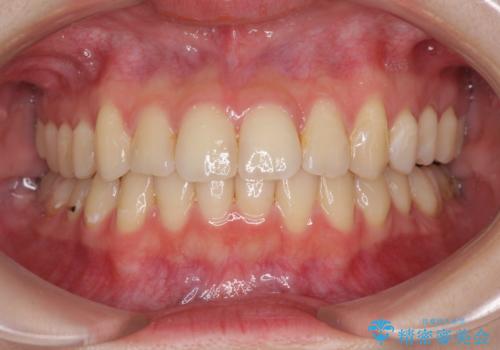

- 上下前歯のデコボコを気にして来院された患者様です。

以前矯正をした後戻りということで、歯列不正はそれほど大きくなかったため、インビザライン・ライトを用いて矯正治療を行うこととしました。

前歯のデコボコが残っており、シミュレーション通りに動いていない部分がありましたが、再矯正であることやご本人の満足いくところまでデコボコが改善されたとのことで、治療を終了することとしました。